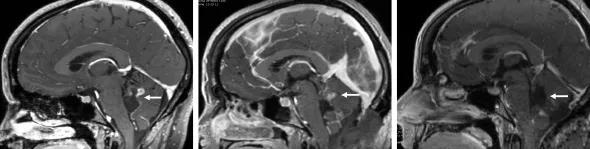

The skull base is one of the human body’s most complex anatomical regions. Five bones come together to create the floor of the cranial cavity through which vital nerves and blood vessels pass. This close proximity and its deep positioning make skull base surgery one of the most challenging areas of neurosurgery.

According to the National Brain Tumor Society, nearly 89,000 primary brain tumors will be diagnosed this year, of which there are more than 100 distinct types. Benign meningiomas are the most common and account for 39% of all primary brain tumors. Approximately 20-30% of these meningiomas occur in the skull base where arachnoid cap cells – the originator cells for meningiomas – are most abundant. Other types of skull base tumors include pituitary adenomas, craniopharyngiomas, which develop near the pituitary gland, and schwannoma, a type of nerve sheath tumor.

According to Dr. Adada, many skull base tumors can be removed using either an endoscopic approach or microscopic surgical techniques combined with small craniotomy. These less invasive procedures include endonasal endoscopic surgery, the supraorbital craniotomy, and the retromastoid craniotomy, among others.

Endonasal endoscopic surgery uses a natural corridor to manage skull base lesions, causing less tissue damage and a quicker recovery. This transnasal technique is used to access the sellar, medial and most of the lateral areas of the skull base. “For many years the cavernous sinus, located behind the eye sockets, was considered ‘no man’s land’ by neurosurgeons, but that is no longer the case,” Dr. Adada notes.

Advances in technology and instrumentation have supported the rapid development of these two surgical approaches, including the endoscope, operating microscope, and the more advanced 3D exoscope. Intraoperative neuronavigation using high-resolution MRI and CT imaging also allows for precise intraoperative localization and the avoidance of critical structures.